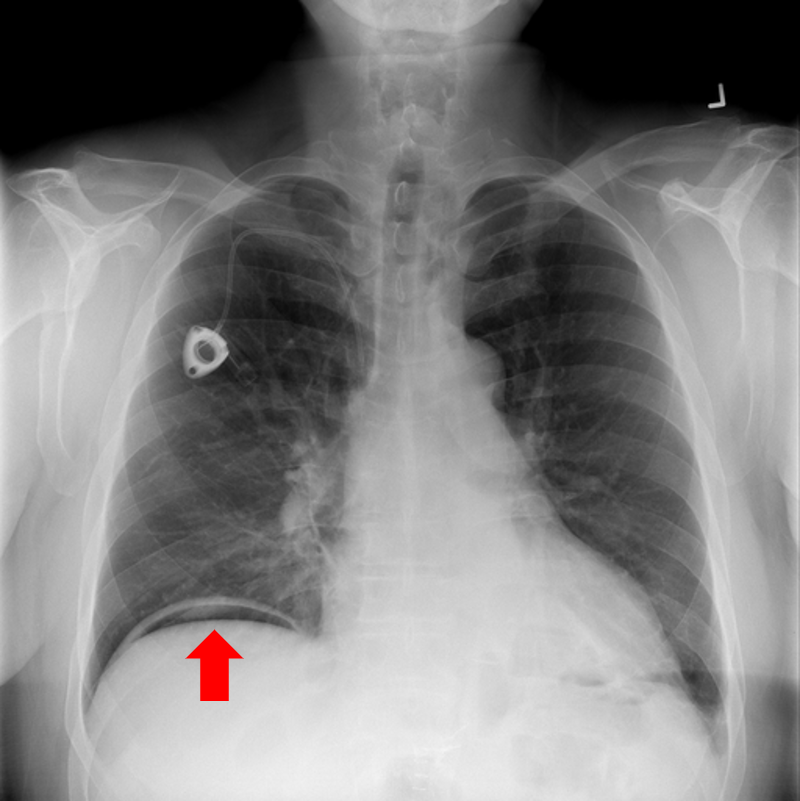

Refer to caption

(a) Pleural effusion

(b) Emphysema

(c) Mediastinal mass

(d) Scoliosis

(e) Multiple bony lesions

(f) Pneumothorax

(g) Heart enlargement

(h) Pneumoperitoneum

Figure 10: Typical CXRs with a lesion from among the top 1,000 CXRs most likely to have an abnormality according to the logarithm posterior probability out of the 13,863 abnormal CXRs excluding those with a pneumonia-like lung opacity. The lesion is indicated with a red arrow if applicable.

Figure 10 shows CXRs suggested to have an abnormality different from pneumonia-like lung opacity with the logarithm posterior probability. These CXRs are the top 1,000 CXRs most likely to have an abnormality out of the 13,863 abnormal CXRs.